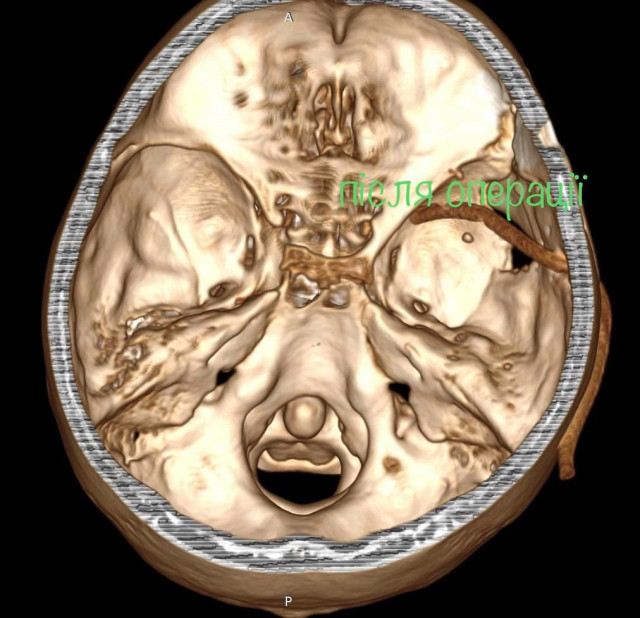

«Ми виконали невідкладну операцію і вилучили стороннє тіло, видалили пошкоджені тканини і відновили цілісність збережених тканин. Добре, що куля зупинилась в 1 см від надзвичайно важливої судини і права скронева частка (яка пошкодилась в результаті травми) – функціонально незначима. Інакше, наш козак був би зовсім іншим, назавжди», – написав Михайло Ловга.